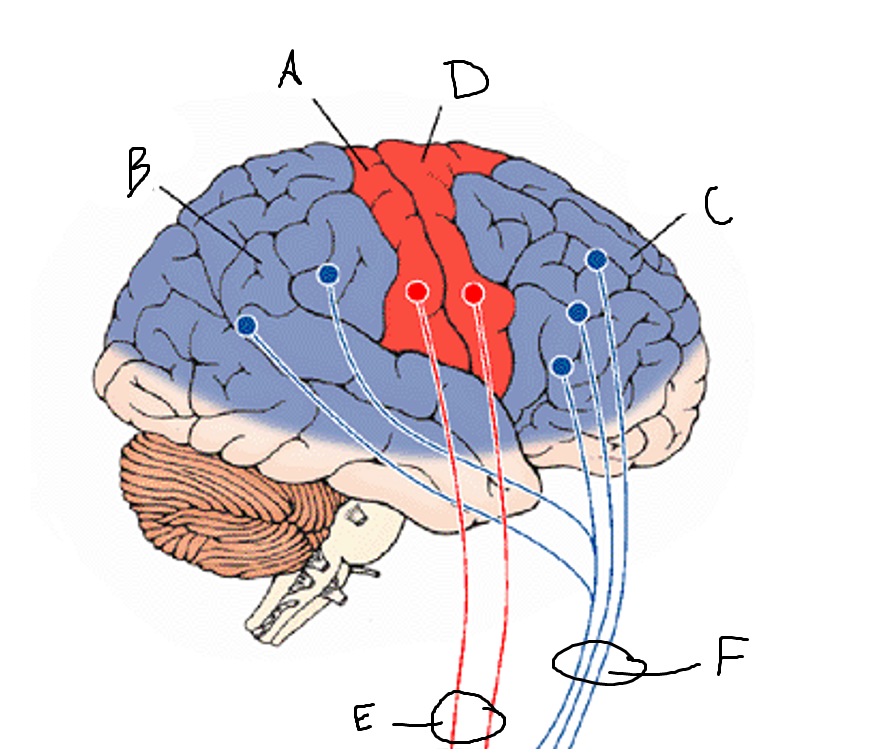

basal ganglia

A

somatosensory cortex

B

parietal association cortex

C

frontal and prefrontal cortices

D

primary motor cortex

E (where are the projections?)

putamen

F (where are the projections?)

caudate